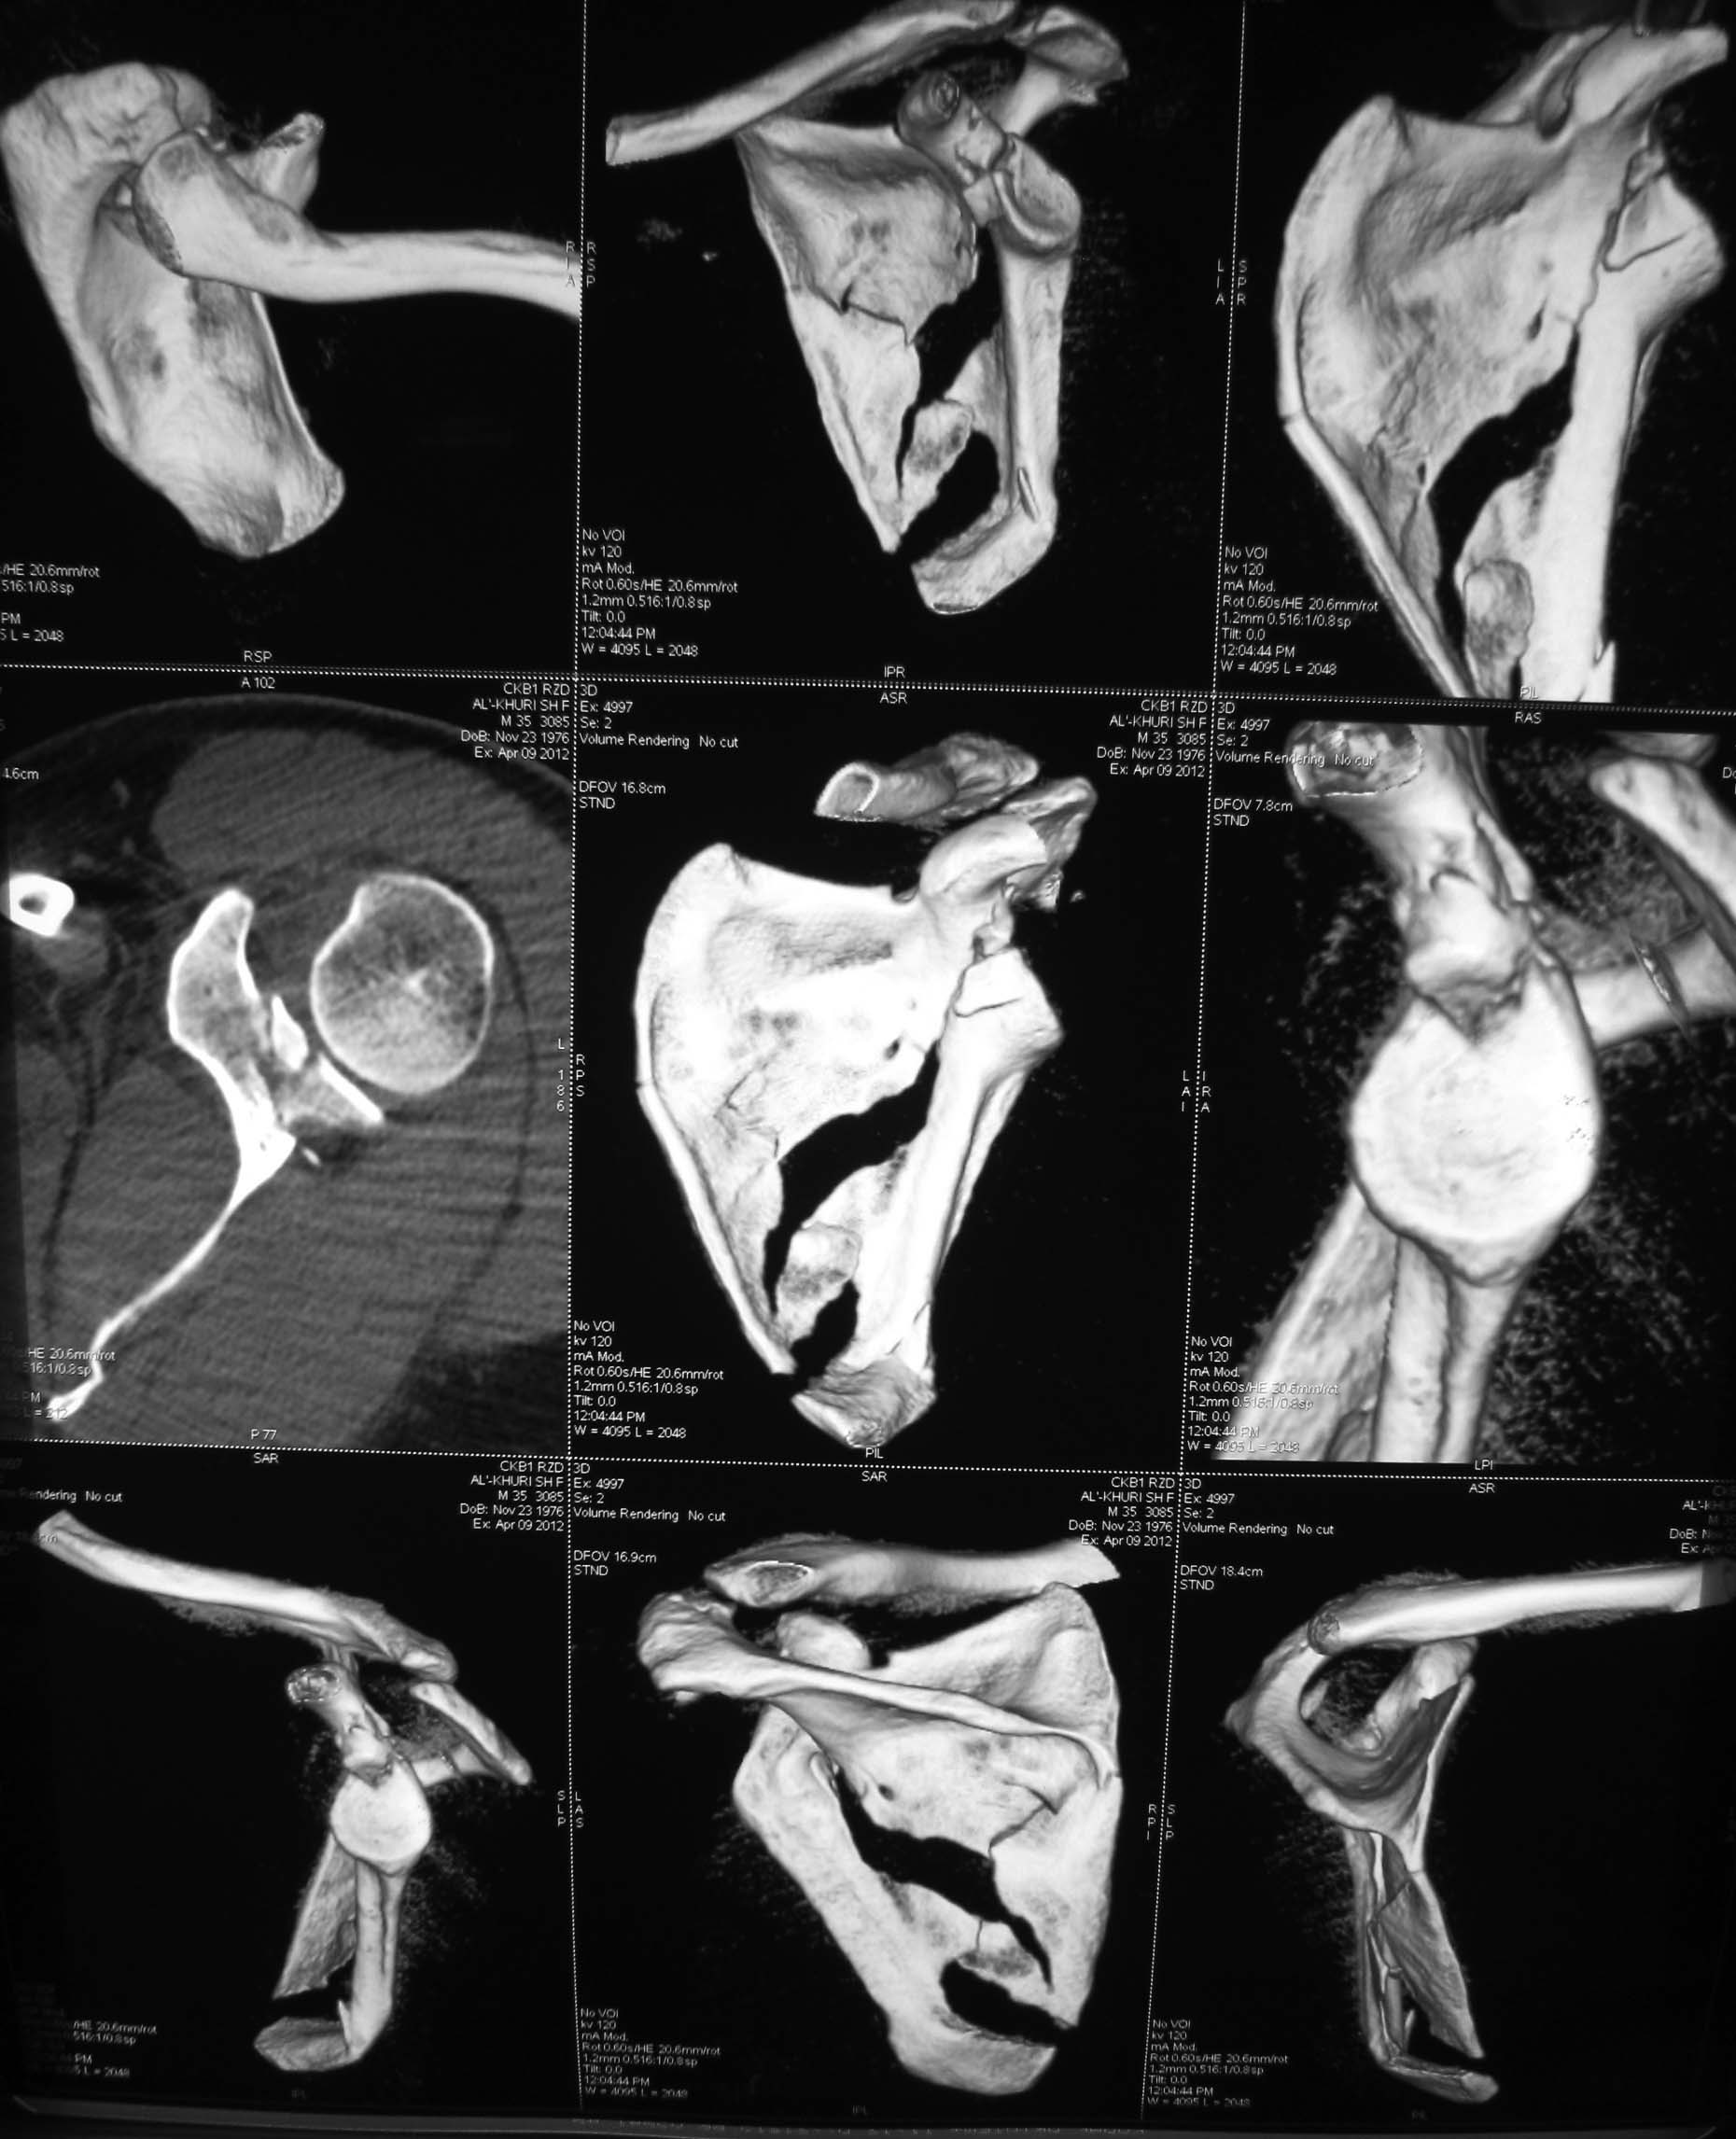

КТ отправляю

Я бы оставил все как есть. ориентация гленоида нормальная, перелом суставной поверхности без существенного смещения

Латеральный край лопатки развернут в антеверсию вместе с суставной впадиной лопатки, плюс суставная впадина при этом мигрировала медиально. В таком случае считаю важным развернуть латеральную "колонну" обратно путем остеосинтеза тела лопатки. Внутрисуставные фрагменты пока загадка. Сами по себе они могут особо не мешать, но там может быть тяжелый SLAP.